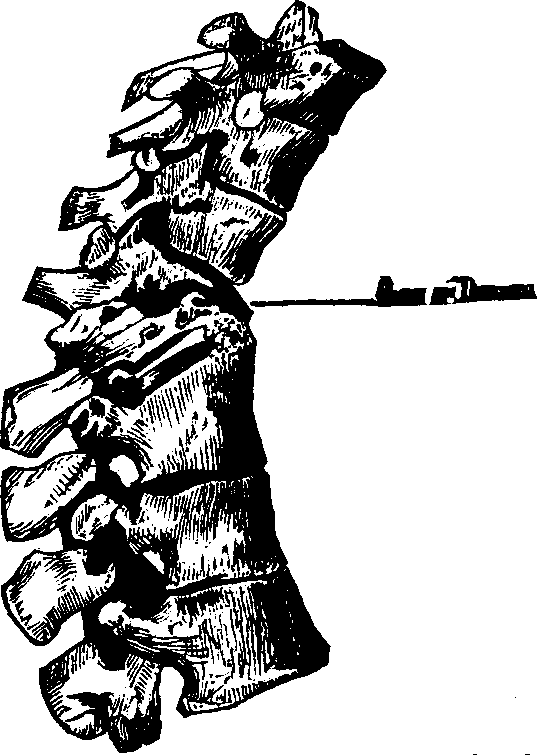

Fig. 10. Flexion, u, Uterus, B, Bladder.

Fig. 11. Version, u, Uterus, B, Bladder.

Flexions and Versions of the Womb. Flexion of the uterus, in which it is bent upon itself, as illustrated in Fig. 10, produces a bending of the cervical canal, constricting or obliterating it, and thus preventing the passage of spermatozoa through it. Version of the uterus [pg 710]in which its top, or fundus, falls either forward against the bladder (anteversion), as illustrated in Fig. 11, or backward against the rectum (retroversion), may close the mouth of the uterus by firmly pressing it against the wall of the vaginal canal, and thus prevent the passage of spermatozoa into the womb. 'The treatment of these several displacements will be considered hereafter. We may here remark, however, that they can be remedied by proper treatment. Our mechanical movements, manipulations, and kneadings are invaluable aids in correcting these displacements.